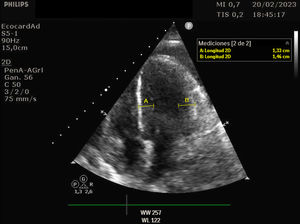

Se trata de una mujer de 41 años con deficiencia humoral y gammapatía monoclonal IgG lambda, que acude al servicio de Urgencias con fiebre y debilidad, siendo diagnosticada de infección respiratoria secundaria a Influenzae A. Veinticuatro horas después ingresa en el servicio de Medicina Intensiva por hipotensión severa, con necesidad de noradrenalina hasta 0,5 ug/kg/min, hipoalbuminemia y hemoconcentración. Se estableció el diagnóstico de síndrome de fuga capilar sistémica con edema intramiocárdico. El síndrome de fuga capilar sistémica es una condición caracterizada por la fuga de plasma y proteínas al compartimento intersticial, y se asocia con gammapatía monoclonal y frecuentemente aparece después de una infección del tracto respiratorio superior, siendo el edema intramiocárdico una complicación poco frecuente. En nuestra paciente, se realizó un ecocardiograma transtorácico al ingreso, mostrando una función ventricular sistólica dentro del límite inferior de la normalidad (FEVI 50-55%), con comportamiento restrictivo, además se evidencia un engrosamiento difuso del miocardio: eje largo paraesternal (fig. 1 y vídeo A), eje corto paraesternal a nivel apical (fig. 2), y plano apical cuatro cámaras (fig. 3), probablemente secundario a edema intramiocárdico, ya que un ecocardiograma transtorácico realizado 1 mes antes mostró grosores normales, eje largo paraesternal (fig. 4). Se prescribió tratamiento con inmunoglobulinas y corticosteroides, pero lamentablemente la paciente falleció 24 horas después del ingreso debido a un shock refractario.